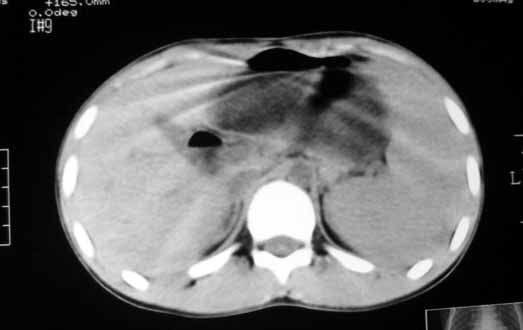

以下是引用zhangzhongshou在2007-5-22 21:04:00的发言:[br]1、脾肿大[br]2、脾脏低密度影,血管瘤?脾梗塞不能除外,建议增强扫描。

以下是引用dyqct在2007-5-22 20:45:00的发言:[br]巨脾,可疑梗塞,建议增强、查血象进一步检查

以下是引用liuyue在2007-5-23 7:57:00的发言:[br]腹主动脉周多个肿大淋巴结,脾大伴三角形低密度影,肠腔积气,考虑:1淋巴瘤2脾大伴梗塞3肠腔积气(肿大淋巴结压迫所致)